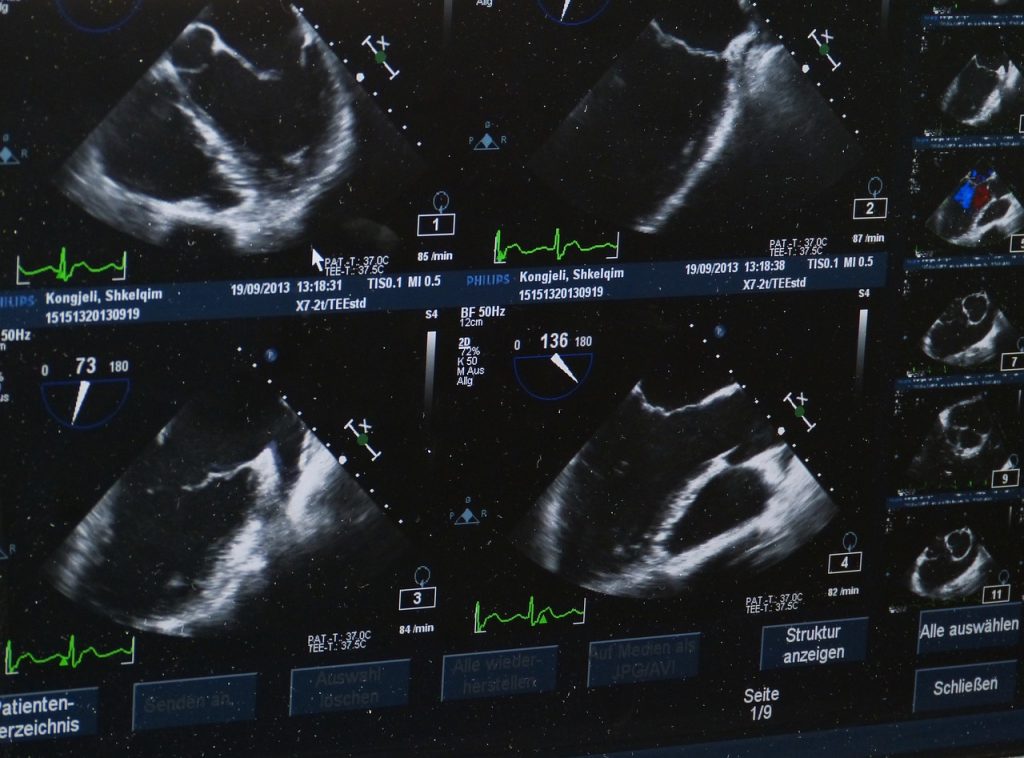

Badanie ultrasonograficzne stawu kolanowego po iniekcji botoksu przeprowadza się przy użyciu wysokowydajnego ultrasonografu, który umożliwia dokładną ocenę struktur anatomicznych oraz ewentualnych zmian patologicznych. Pacjent jest zazwyczaj badany w pozycji leżącej, zgiętej lub wyprostowanej w stawie kolanowym, co umożliwia pełną ocenę zakresu ruchu stawu.

Podczas badania USG ocenia się m.in. grubość chrząstki stawowej, obecność wysięków stawowych, stan ścięgien i więzadeł oraz ewentualne zmiany zwyrodnieniowe. Dodatkowo, ocenia się również umiejscowienie i rozprzestrzenienie iniekcji botoksu w stawie kolanowym.